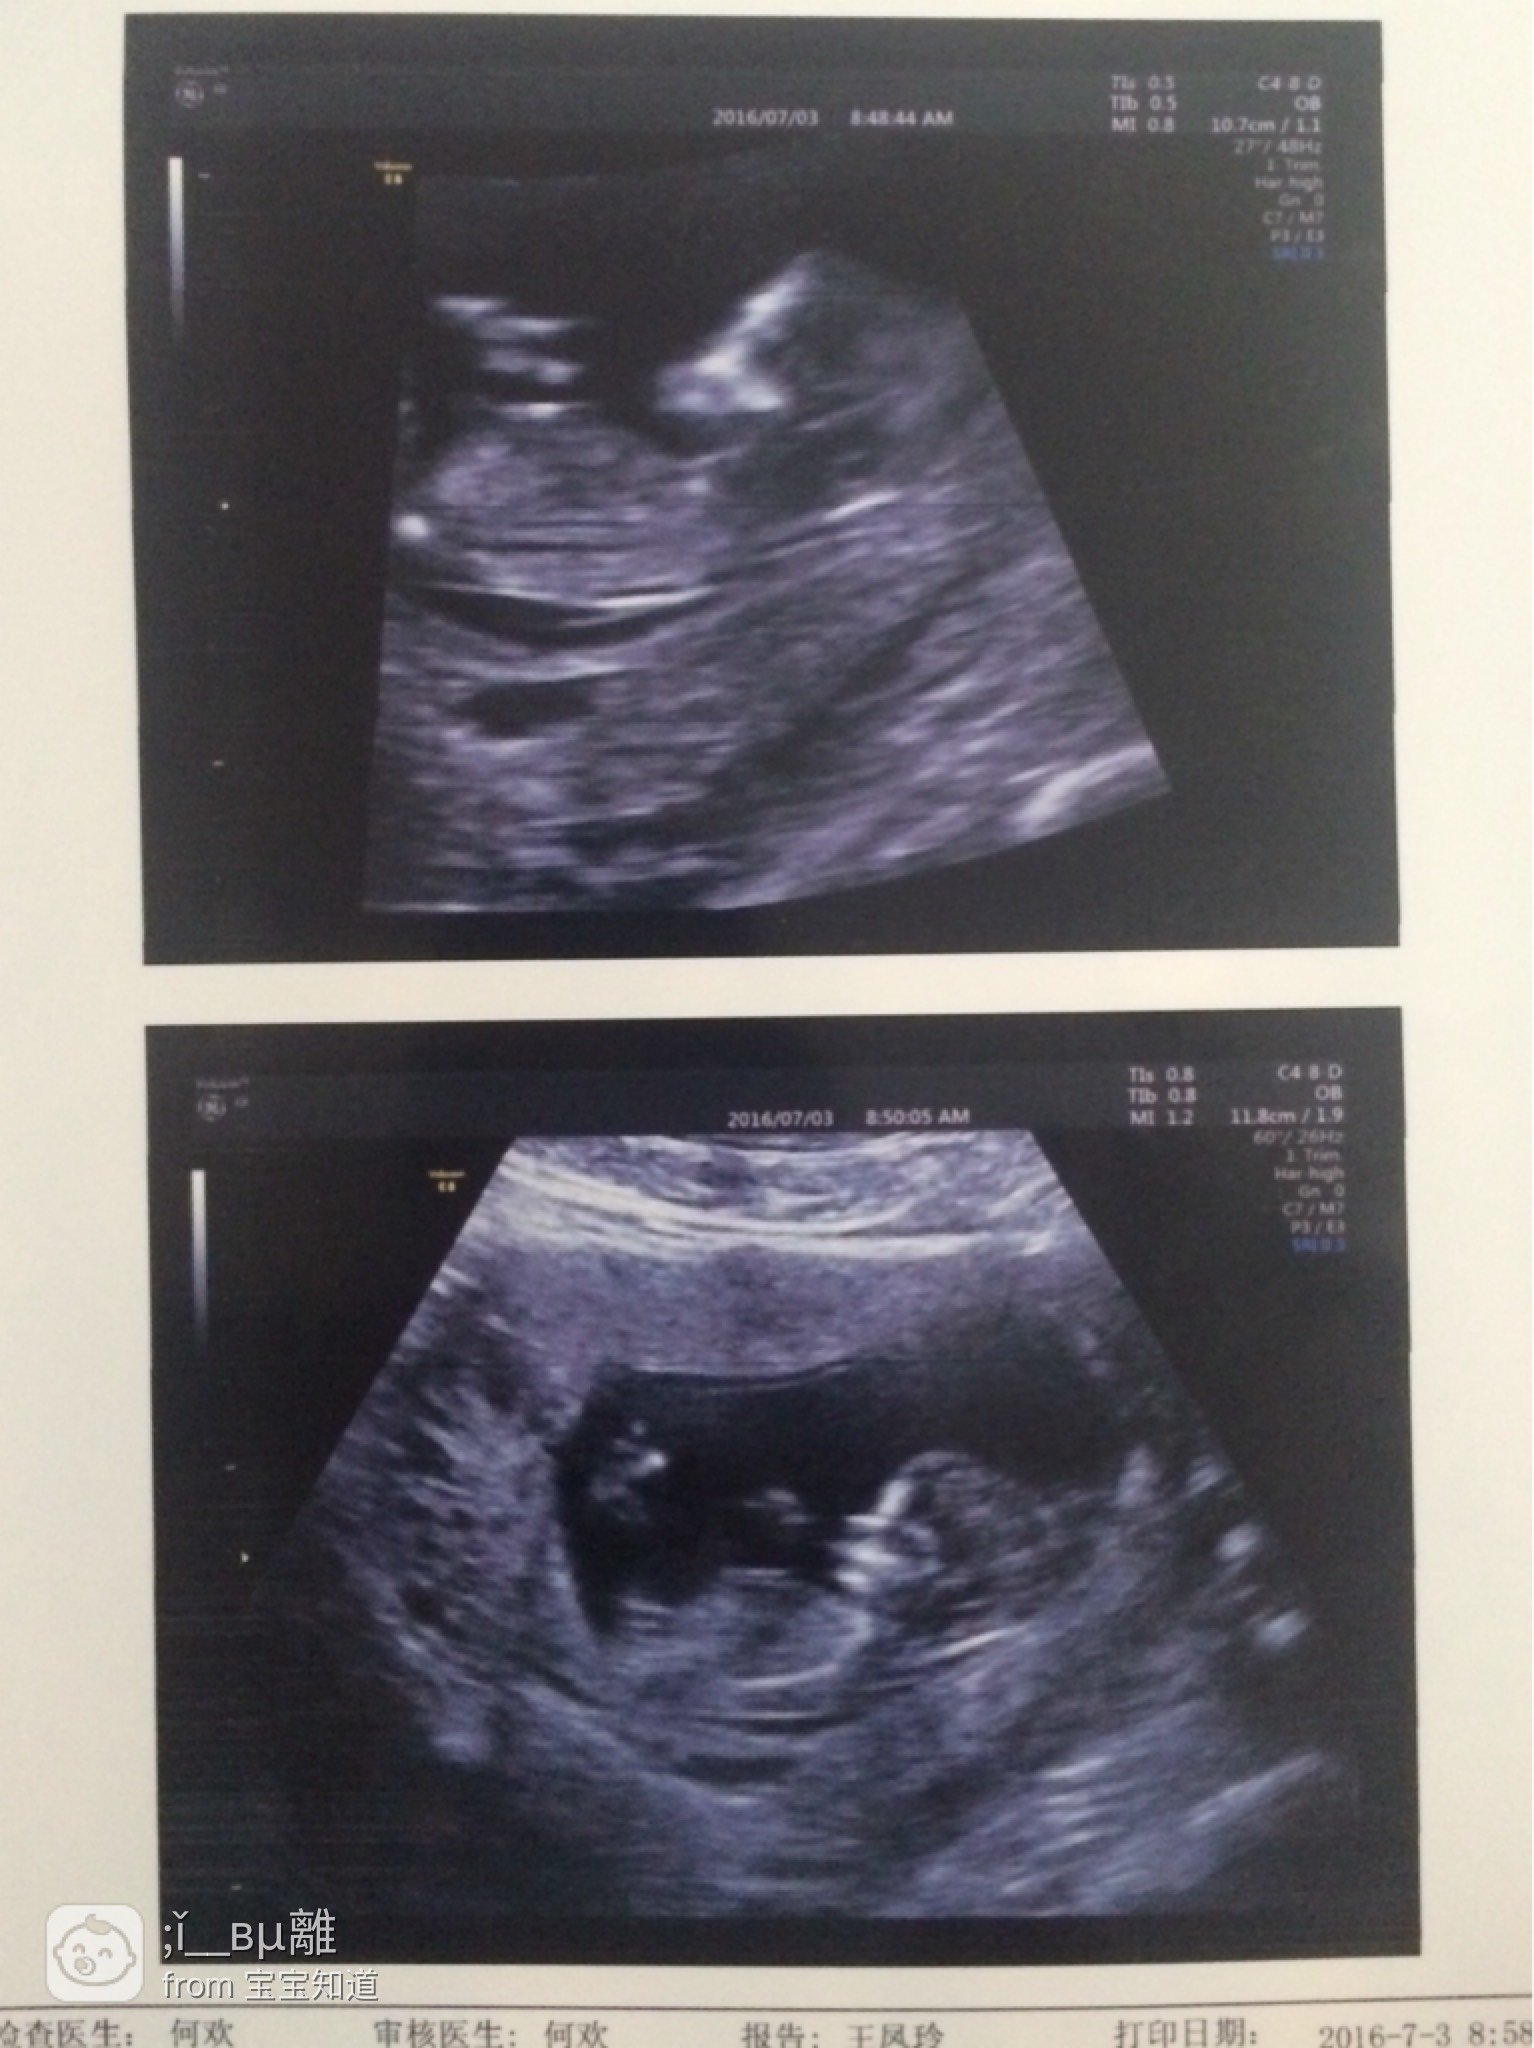

12周NT,这是撒意思啊?还让19日做无创DNA~

亲们帮忙看看这个5mm带状无回声是撒意思啊?这个心情就以糟像荒旧佳做过山车了都!~法搁希望宝宝健康~先谢谢各位了!~

大于3毫米就要做无创,羊穿,怕宝宝染色体不好

考虑是否畸形,我的9毫米过段流产了~没继续下去,结果胚胎做出来真的发育不好

3毫米以内正常能自行吸收…大于3难说是不是他不好